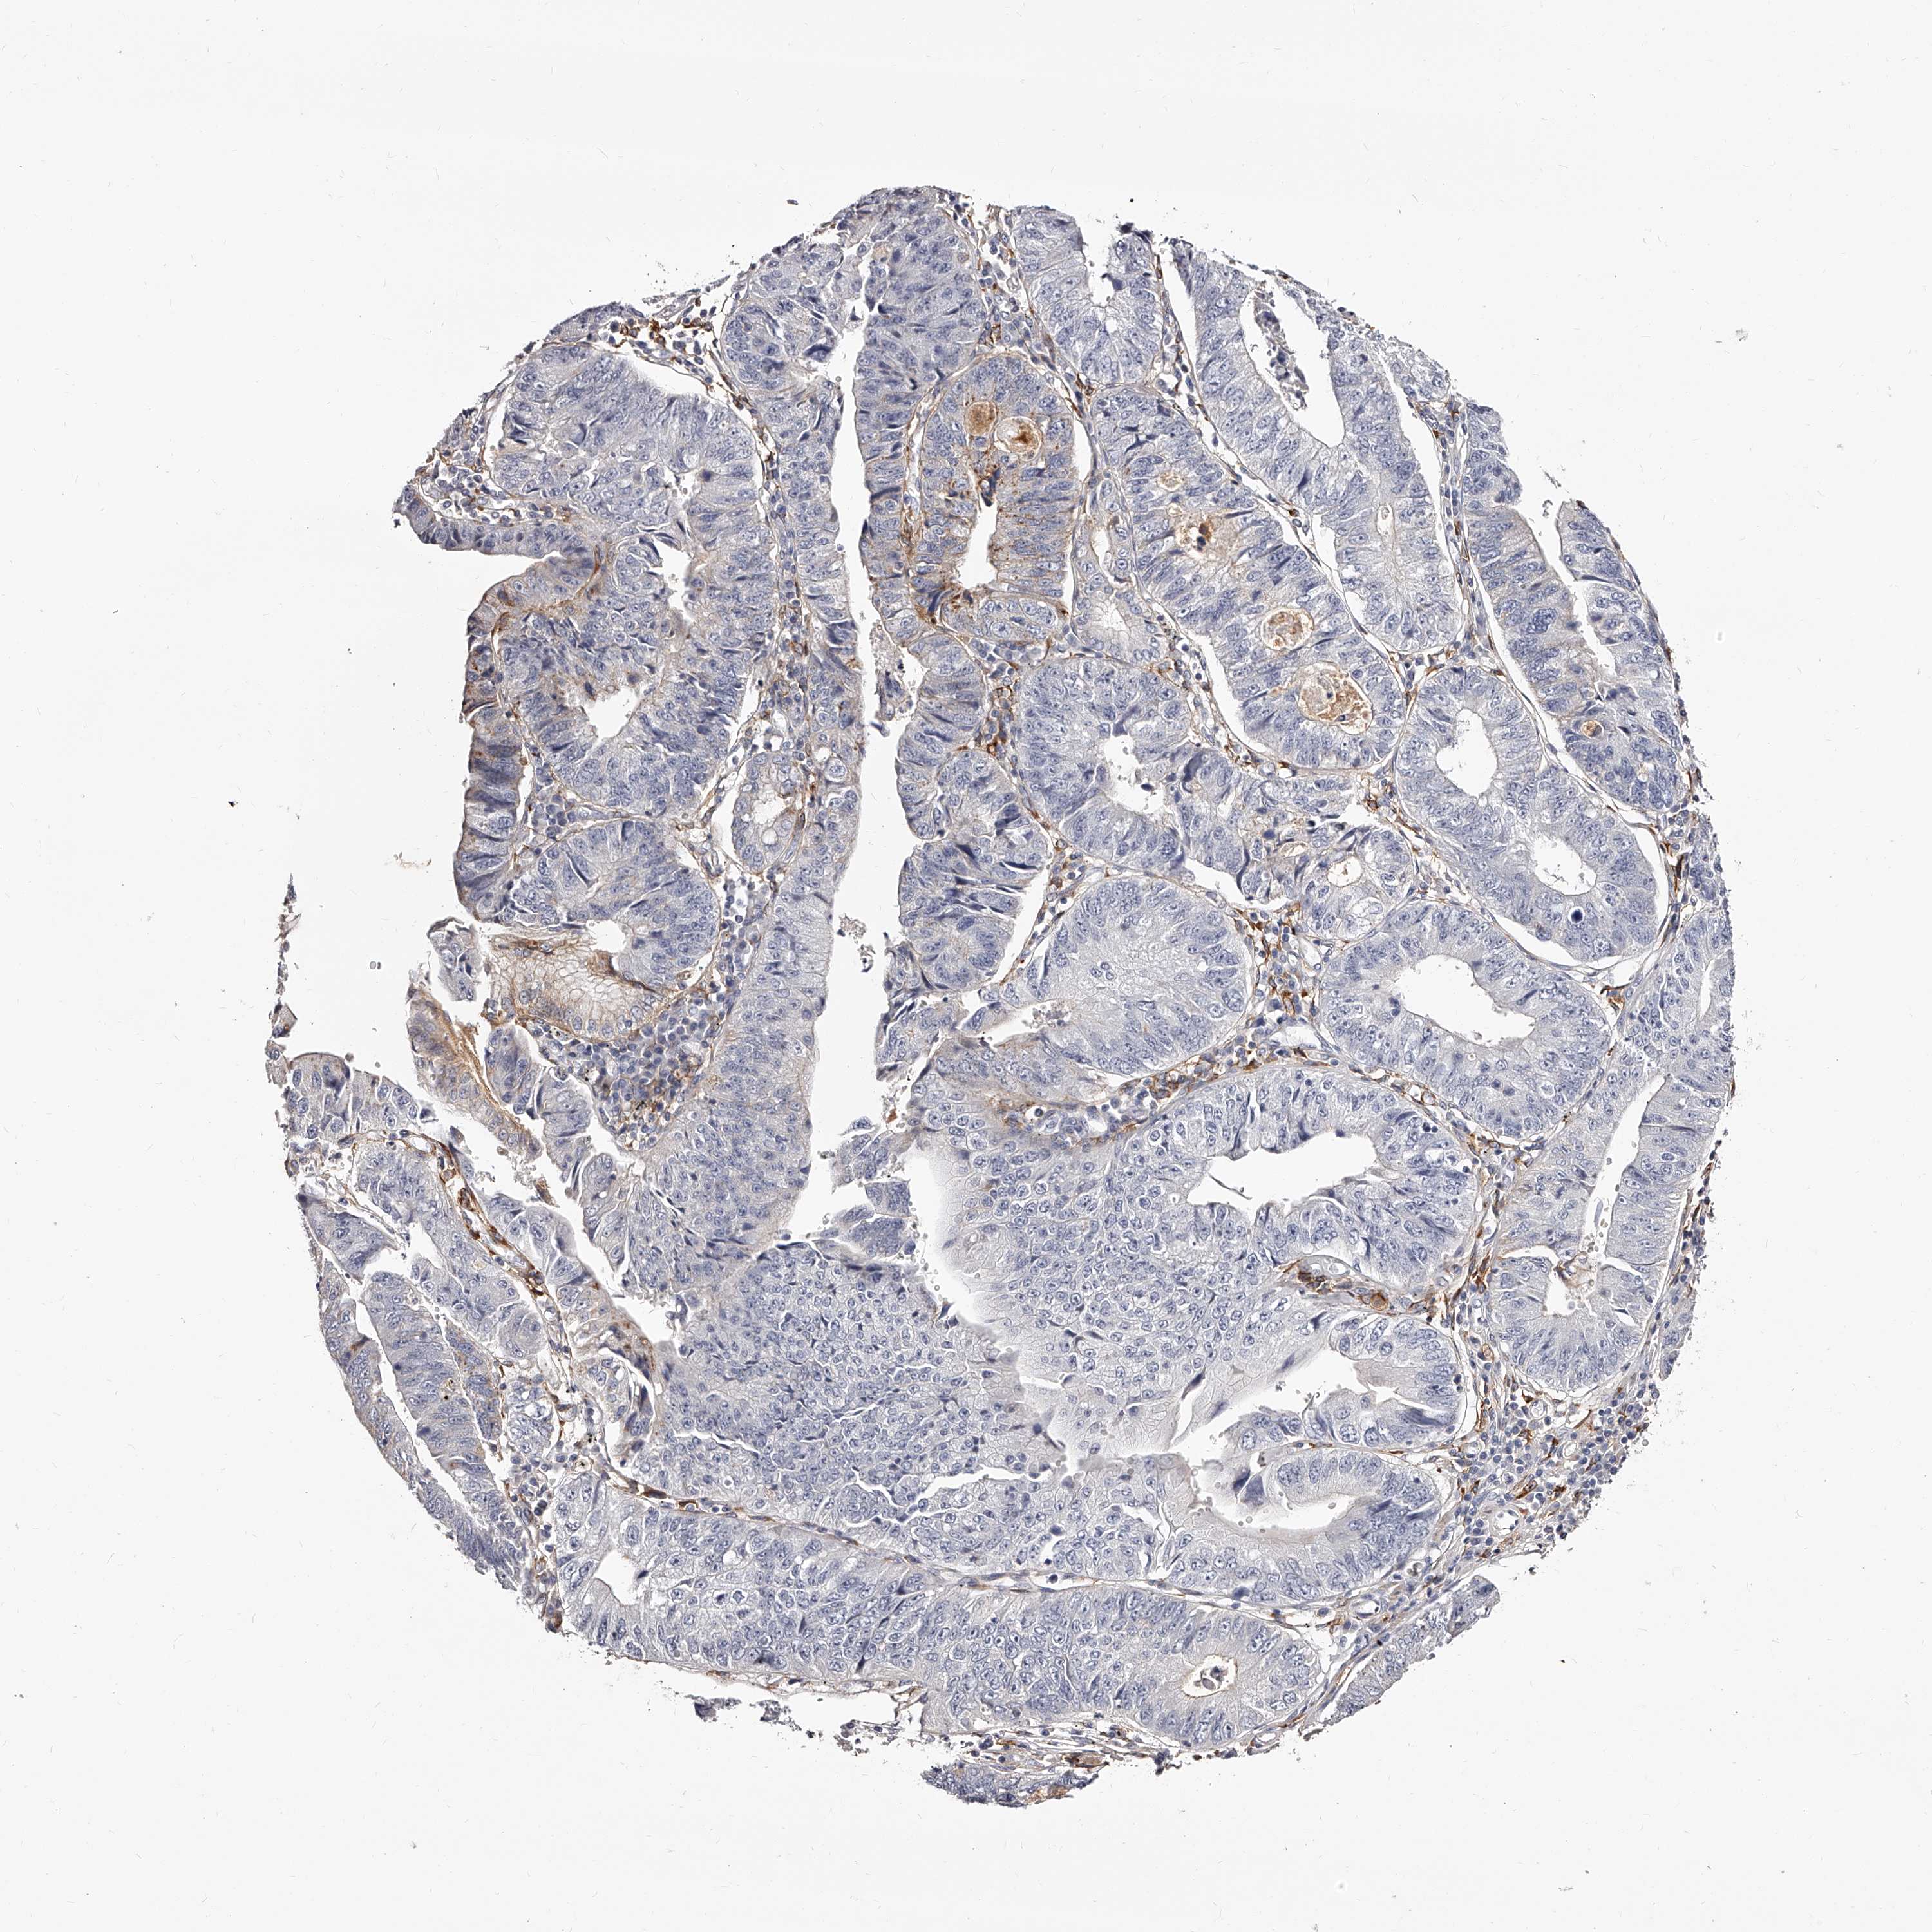

STOMACH CANCER - Protein expressioni

A mouse-over function shows sample information and annotation data. Click on an image to view it in a full screen mode. Samples can be filtered based on level of antibody staining by selecting one or several of the following categories: high, medium, low and not detected. The assay and annotation is described here.

Note that samples used for immunohistochemistry by the Human Protein Atlas do not correspond to samples in the TCGA dataset.

Antibody stainingi

Antibody staining in the annotated cell types in the current human tissue is reported as not detected, low, medium, or high, based on conventional immunohistochemistry profiling in selected tissues. This score is based on the combination of the staining intensity and fraction of stained cells.

Each image is clickable and will lead to virtual microscopy that enables deeper exploration of all samples and also displays staining intensity scores, fraction scores and subcellular localization as well as patient and tissue information for each sample.

Antibody HPA028900

Antibody CAB002508

Staining

High

Medium

Low

Not detected

Intensity

Strong

Moderate

Weak

Negative

Quantity

>75%

75%-25%

<25%

None

Location

Nuclear

Cytoplasmic/membranous

Cytoplasmic/membranous,nuclear

Adenocarcinoma, NOS